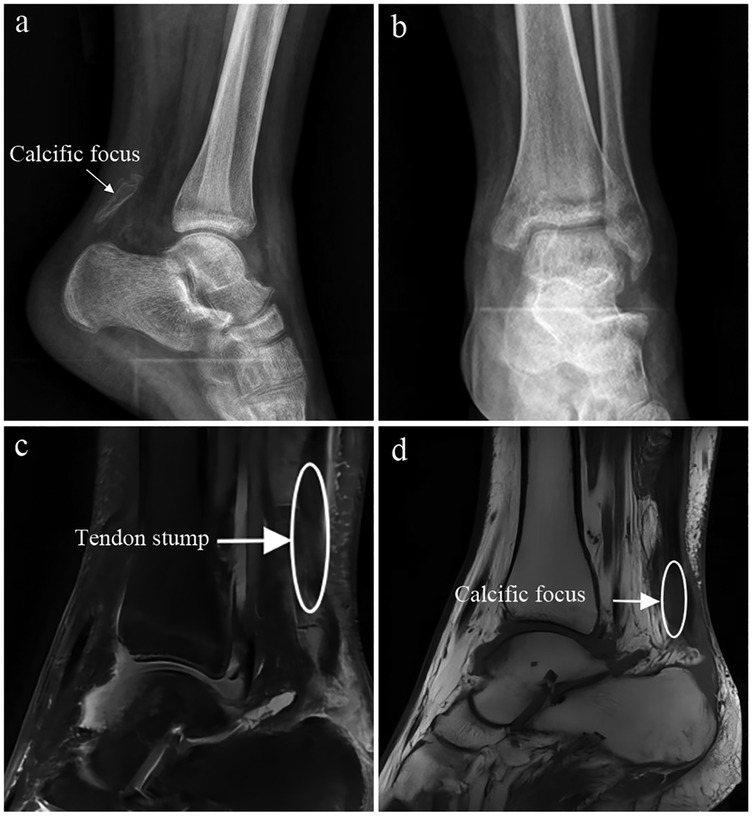

Introduction: The Achilles tendon is the largest tendon in the human body and is prone to rupture when subjected to excessive dorsiflexion trauma of the ankle joint. The primary goal of treatment is to restore limb function; however, there remains considerable debate regarding the optimal management strategy. Patient Concerns: We report a patient presenting with chronic Achilles tendon rupture accompanied by calcification of the tendon, which caused persistent pain and functional limitation of the affected limb. Diagnosis: Chronic Achilles tendon rupture with associated tendon calcification, with a tendon defect measuring approximately 6 cm on preoperative imaging, confirmed by clinical examination and imaging evaluation. Interventions: The patient underwent surgical removal of the calcified lesion, followed by reconstruction of the tendon defect using a gastrocnemius aponeurosis flap combined with the Achilles tendon sheath. Outcomes: Postoperative recovery was favorable, and at the 6-month follow-up, the patient achieved satisfactory ankle function with an AOFAS score of 89, a VISA-A score of 91, and an ATRS score of 90. At the 12-month follow-up, functional outcomes remained stable, with an AOFAS score of 95, a VISA-A score of 96, and an ATRS score of 94, confirming sustained recovery and tendon integrity. Conclusion: This case highlights a feasible surgical strategy for chronic Achilles tendon rupture with calcification, which may provide an alternative approach for tendon reconstruction in patients with sheath proliferation and calcified lesions.